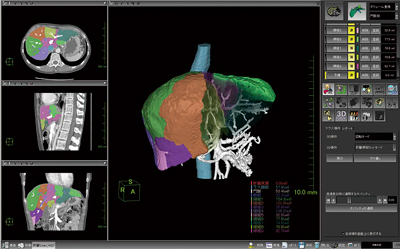

6.肝臓解析

“肝臓解析”はドナーの肝実質容積測定など,生体肝移植術前シミュレーションや術後の経過診断を支援するソフトウェアである(図8)。肝実質を自動的に抽出することが可能で,下大静脈・門脈・肝静脈などを除いた肝実質ボリュームを算出することが可能である。当社特許技術を搭載しており,各血管の肝実質における支配領域をセミオートにて抽出可能である。肝右葉・左葉区別や,区域別(S1〜S8)のボリュームも計測可能である。

厚生労働省の先進医療の各技術の概要についての60番に,肝切除手術における画像支援ナビゲーションの項目(2010年4月1日現在)があり,肝切除シミュレーションを行うことで安全性の向上に寄与するとしており,その重要度がうかがえる。

図8 肝臓解析